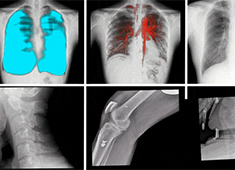

拍攝全脊柱X光片 長骨拼接技術和一板成像的區別

出于對全脊柱X光片的拍攝需求,DR長骨拼接和大平板一板成像這兩項技術應運而生。長骨拼接技術是在DR自動控制程序模式下,通過多次連續曝光及圖像采集(6至8次),將多幅有重疊部分的圖像無縫拼接成一幅連貫的整體圖像。...

骨科手術C臂機為瑞麗市人民醫院實現影像設備升級

瑞麗市人民醫院為提升精準診斷水平和整體服務質量,升級了影像設備,引進普愛醫療品牌的骨科手術C臂機。高端智能影像的加入,助力醫院為患者提供更加精準、高效的診療服務。...